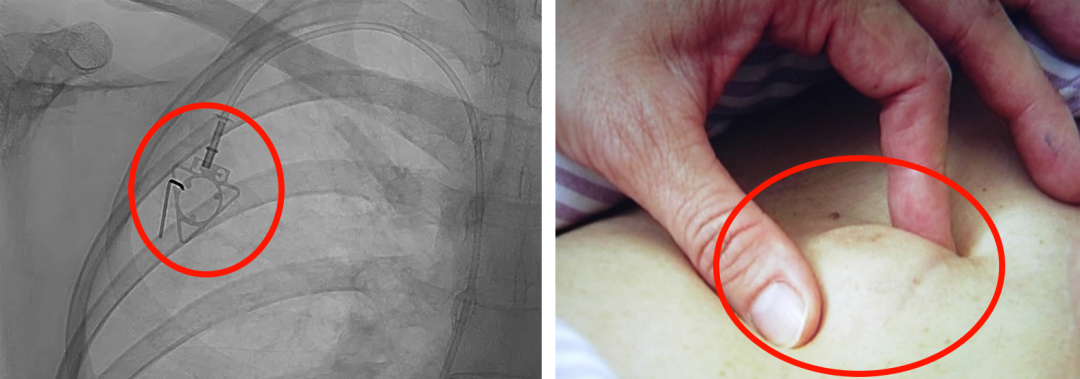

輸液港,臨床上也稱為PORT,是為了減輕藥物對(duì)患者血管刺激而置入體內(nèi)的專業(yè)輸液裝置。它分為三部分:無(wú)損傷針、置入靜脈的導(dǎo)管、埋藏在皮下與輸液針連接的注射座(港體)。注射座連接插入大靜脈的導(dǎo)管形成長(zhǎng)期血管通路,發(fā)揮類似港口的作用,故稱作“輸液港”。

(1)輸液港輸注藥物直達(dá)大血管,手臂不會(huì)產(chǎn)生明顯的不適。由于每次穿刺的是皮下置入的港,可以減少針頭對(duì)血管的刺入次數(shù),操作簡(jiǎn)單,對(duì)患者的血管起到保護(hù)作用;

(2)輸液港放置在皮下,不易被別人發(fā)現(xiàn),具有隱秘性;洗澡,日常生活不受限制;

(3)由于輸液港完全埋藏在體內(nèi),不易受到感染;